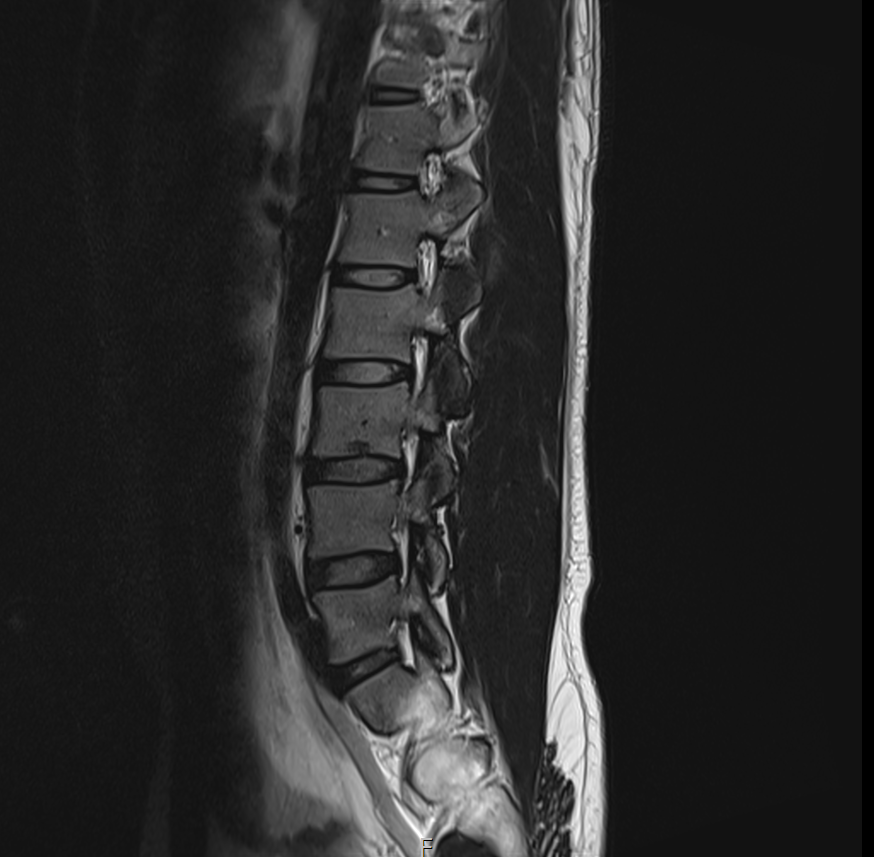

현재

• 3번 째 사진

1년 전 사진에 비해 허리디스크 상황이 악화된 것으로 생각됩니다. 다리저림은 이로 인한 증상으로 생각됩니다.

그러나, 말씀하신 내용과 검사결과만으로는 교통사고와의 연관성에 대해 단정지어 말하기는 어렵습니다. 증상이 점차 악화되어 발생한 것인지, 교통사고에 의해 갑자기 악화된 것인지에 대한 판단이 추가로 필요하겠습니다.